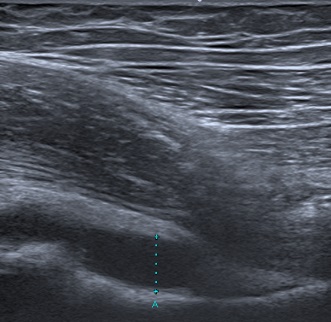

Se realiza un hemograma con leucocitosis de 14 550/mm3 (10 630/mm3 neutrófilos, 2300/mm3 linfocitos) y una proteína C reactiva (PCR) de 69,9 mg/l, así como líquido articular en la ecografía de partes blandas (Fig. 1) y en la resonancia magnética (RM) derrame articular de cadera derecha con engrosamiento sinovial y afectación acetabular con edema de los músculos obturadores y psoas-ilíaco ipsilaterales (Fig. 2), datos sugestivos de artritis de cadera.